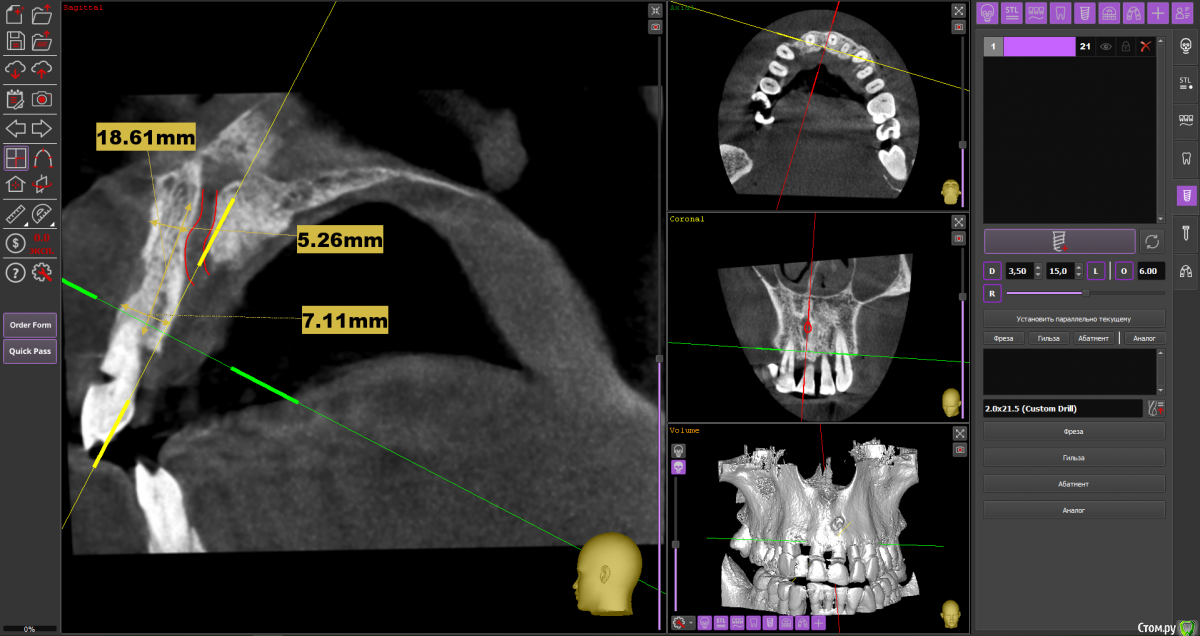

almaz7888 Опубликовано 28 января, 2021 Поделиться Опубликовано 28 января, 2021 Доброе утро коллеги! Планирую одномоментную имплантацию в область 2.1 зуба ( AnyRidge 3.5*11.5). В области апекса костный дефект. Думаю заполнить ксенографтом и перекрыть резорбируемой мембраной 1.5*2.0. Думал насчет спейсера Стоит ли такой имплант сразу нагрузить? или же лучше сделать адгезивный мост. Ссылка на комментарий

alboard Опубликовано 28 января, 2021 Поделиться Опубликовано 28 января, 2021 В том положении, которое на кт, сомневаюсь, что получите торк и сможете нагрузить... Взять подлиннее, поставить небнее и заглубить еще 4 Ссылка на комментарий

almaz7888 Опубликовано 28 января, 2021 Автор Поделиться Опубликовано 28 января, 2021 Спасибо, тогда возьму 3.5*15. А резцовый нерв коагулирую и заполняю канал графтом или же можно без прижигания обойтись? Ссылка на комментарий